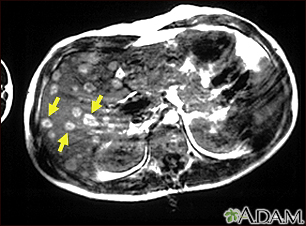

Melanoma of the liver - MRI scan